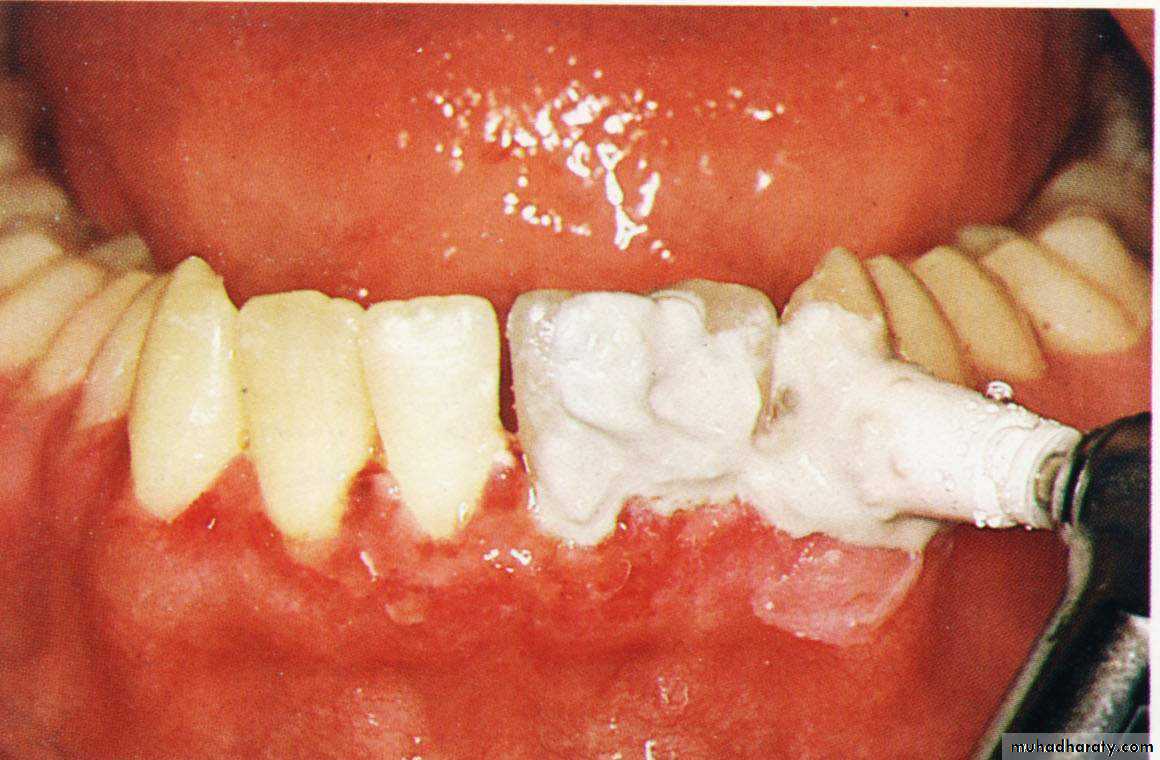

8. Dressing of the wound for (7 – 10 days).